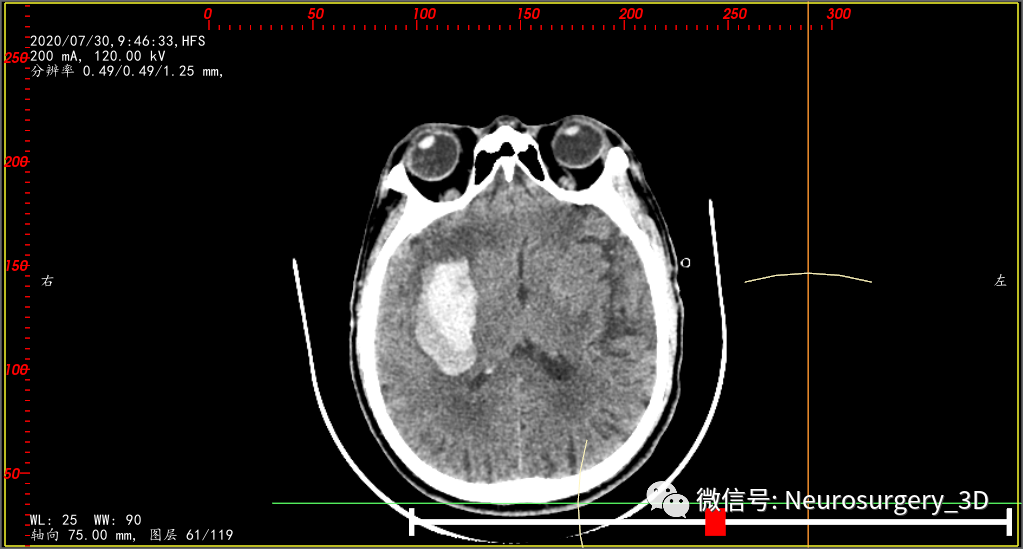

某某陈(**0723710**),男,74岁,以“突发性左侧肢体运动障碍伴意识不清2小时余”于2020年7月28日00:35入院,GCS 11分,入院CT示:右侧基底节脑出血 ,量约15ml。

入院时CT:

两天后的CT复查(2020年7月30日9:46)并测量不同区域的CT阈值,三维重建阈值选择45-100,包含低密度血肿区域。

是活动性出血吗?对比脑部活动性出血CT征象,一些文献报道:CT混杂征是由Li等在2015年提出的一种预测血肿扩大的影像标记,主要是指(1)血肿内存在边界分明的高低密度两种成分,(2)两种成分CT值至少相差18HU,且(3)低密度成分不包含于高密度成分中的一种征象。其形成的机制是血肿内凝固的血块在CT上呈现高密度,而低密度区域可能是由于破裂的血管仍在持续出血,血液尚未凝固所致。(下符CT混杂征片)

对比上述文献1、2、3还真像活动性出血,血肿较前两次CT检查又有增大现象,如果考虑活动性出血,手术方案无疑选择开瓣血肿清除了,年龄、身体耐术力、基础疾病等种种影响因素都是在活动性出血因素之后考虑的次要因素。